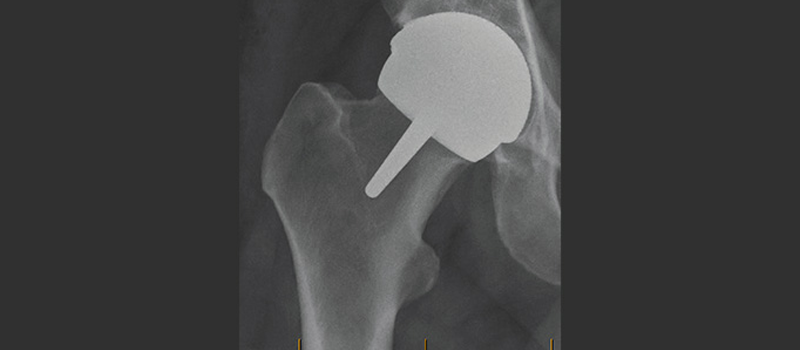

During a hip resurfacing surgery, the patient is placed under general anesthesia. An incision is made to access the hip joint. Unlike THR, where the head of the femur is completely removed, in hip resurfacing, the femoral head is preserved. The damaged surface of the femoral head is reshaped to fit a metal cap, which is made of cobalt-chromium alloy and is designed to mimic the shape of the natural femoral head. The metal cap is then fixed in place with bone cement or a press-fit technique.

In the acetabulum (the socket), the damaged cartilage is removed, and the socket is prepared to receive a metal cup. The metal cup is also made of cobalt-chromium alloy and is implanted into the socket, creating a new bearing surface. The metal-on-metal articulation allows for smooth movement and low wear.